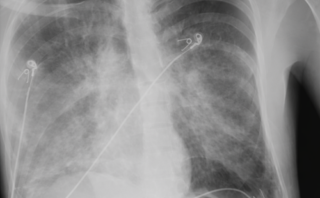

Radiografía de tórax

- Aumento de trama bronquial

- Engrosamiento parahiliar

👉 Interpretación: Cambios crónicos probablemente asociados a exposición a humo de leña.